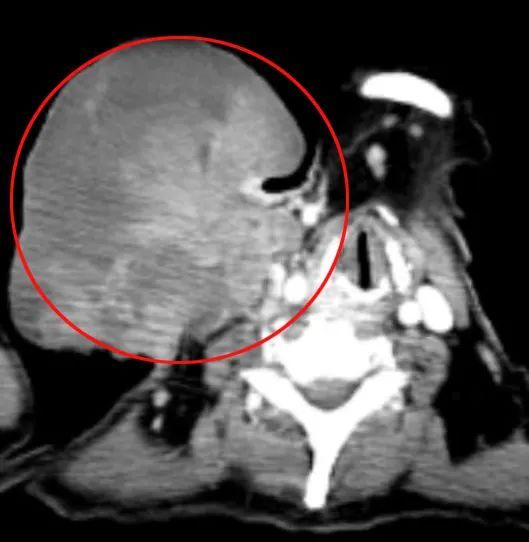

今年6月,赵阿婆一家来到瑞金医院嘉定院区普外科吴庆华专家门诊。吴医生详细询问病史,原来赵阿婆15年前曾经在外院做过甲状腺癌根治术,术后声音嘶哑,后来肿瘤还是复发导致肝肺转移。CT片上看到甲状腺癌在颈部侵犯气管导致狭窄,广泛侵犯食管颈前肌群、胸锁乳突肌及颈内静脉,而且分期为比较罕见的IVB期。同时患者还存在严重细菌感染、电解质紊乱、重度贫血和重度低蛋白血症等各种问题。

吴医生查看赵阿婆颈部重重敷料包裹下的肿瘤,发现肿瘤约15×8×8cm大小,已经出血感染坏死腥臭明显,随时可能出现出血感染,甚至压迫窒息。看着古稀之年、痛苦不堪的病人,吴医生综合判断病情,认为病患虽为甲状腺乳头状癌晚期,但病人没有显著恶液质表现,在充分支持下还是具有局部手术指征的。

赵阿婆CT图像下的肿瘤如同一枚“炸弹”